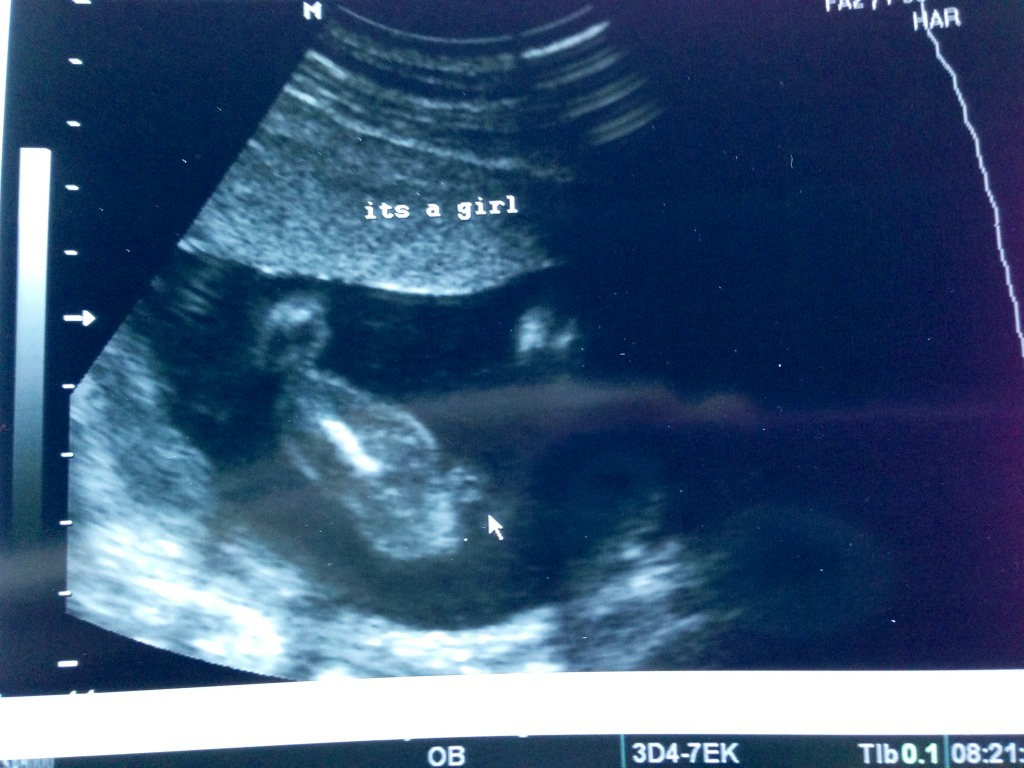

I had an ultrasound today and couldn't see her side profile in 2d only her facing us..

Looks like a typical potty shot to me

Yeah I just wondering cause my first daughters was super clear lol